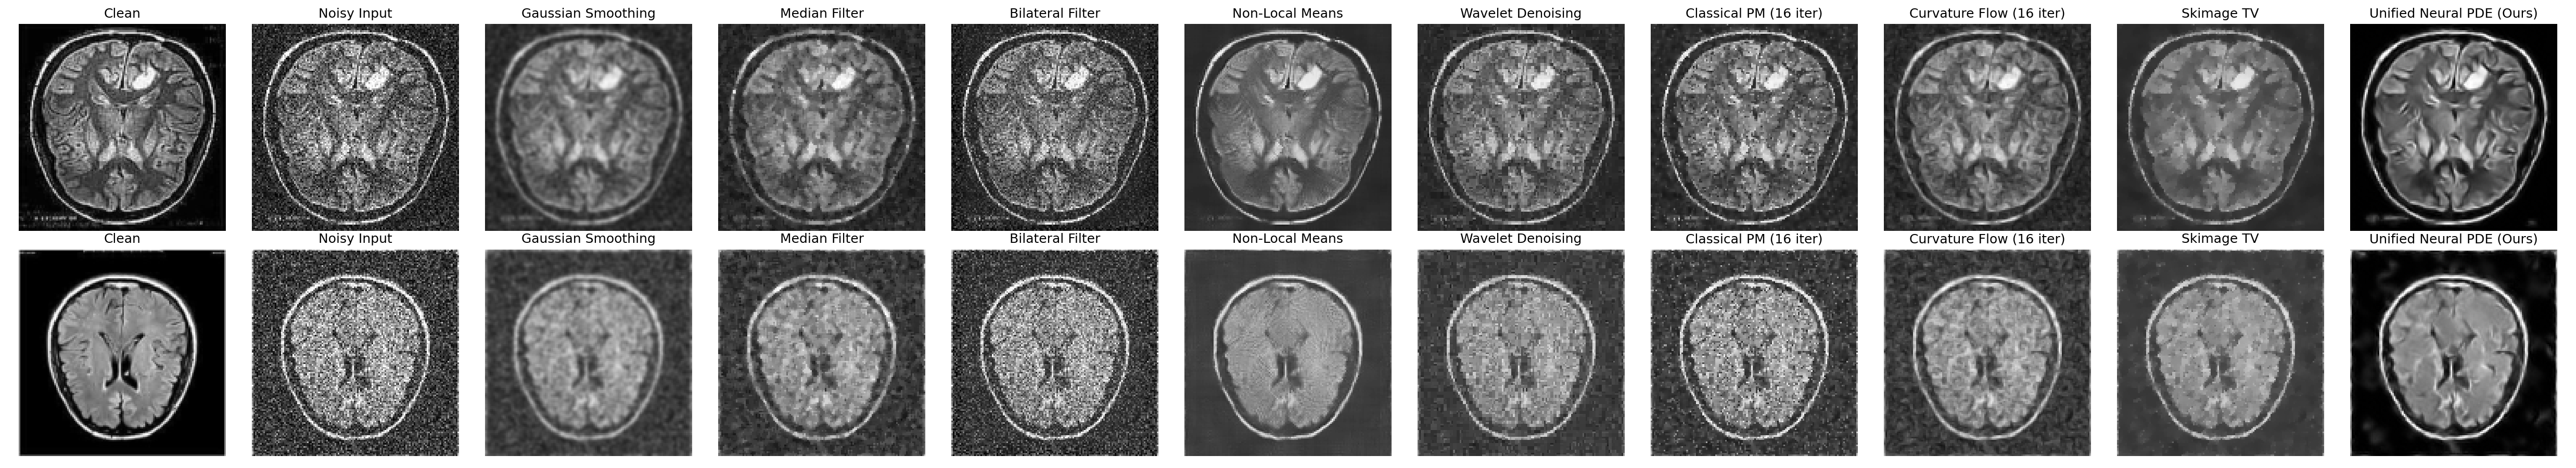

Full Method Grid

Full denoising comparison grid

Final Comparison

The learned PDE model substantially outperforms the classical denoising baselines. The plain U-Net baseline is included as a stronger neural comparison and achieves the best raw denoising metrics.

Method PSNR SSIM Edge MSE

Noisy Input17.7110.4250.194

Gaussian Smoothing19.0110.5520.185

Median Filter19.5380.5210.136

Bilateral Filter18.9550.4630.136

Non-Local Means20.3930.5850.087

Wavelet Denoising19.5190.5300.106

Skimage TV19.4820.5700.134

Curvature Flow19.9850.5600.113

Classical PM19.6350.5390.106

Unified Neural PDE24.8530.7190.056

Plain U-Net Baseline25.8750.7590.053

Higher PSNR and SSIM are better. Lower Edge MSE is better.